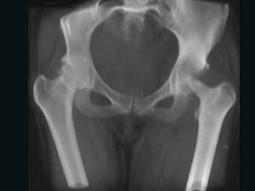

女,27岁,双侧髋部疼痛,肿胀2个月余,继往有髋部外伤史,请结合影像学检查,选出最可能的诊断 ( )A、慢性骨脓肿B、骨结核C、股骨头骨折...